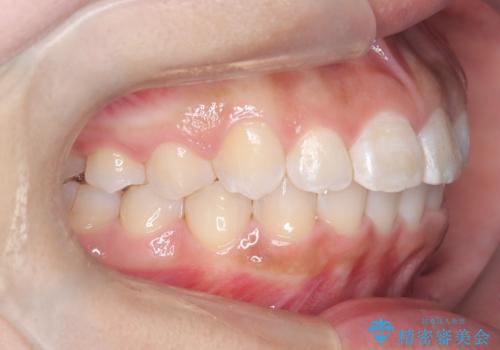

マウスピース矯正で前歯のガタツキを改善! ワイヤー矯正併用でかみ合わせもしっかり治します

- 前歯のガタツキが気になると来院されました。

マウスピース矯正治療を選択しました。

前歯のガタツキを改善する治療法として、マウスピース矯正が適していることが多いです。

マウスピース矯正は、金属製のブラケットやワイヤーを使用せずに、透明なマウスピースを装着して歯を移動させる方法です。そのため、目立たず、痛みも少ないです。

この症例では、奥歯のかみ合わせの改善を目的にワイヤー矯正を併用しました。奥歯のかみ合わせをより緊密にするため、また短期間に治療するためにはワイヤー矯正が適していることがあります。